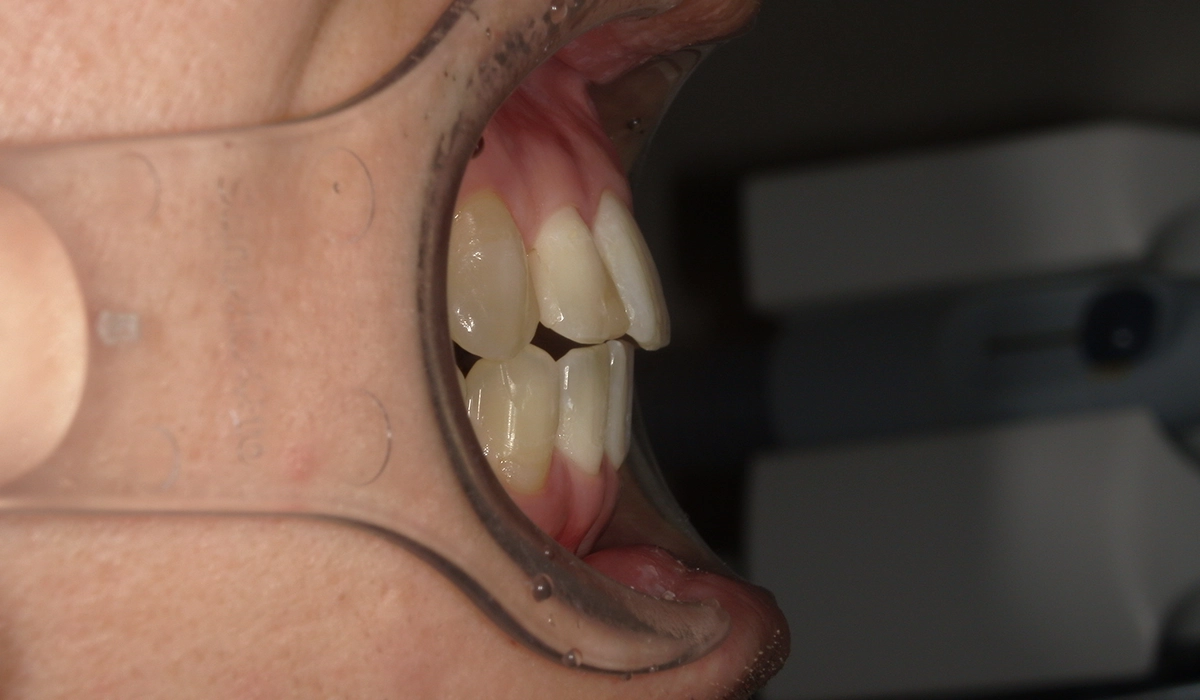

術前:左側

術後:左側